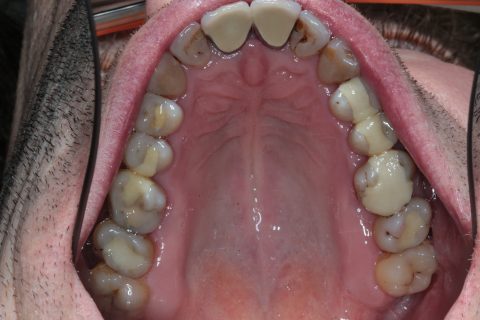

Composite Füllung

| Gesetzliche Kassen | vollständige Übernahme bei Zahnhalsfüllungen u. normalen Frontzahnfüllungen Zuzahlung bei Seitenfüllungen ca. 40,- bis 80,- EUR. Bei großflächigen Füllungen: nicht empfehlenswert, besser Krone/Teilkrone |

| Vorteile | gutes Aussehen, gute Haltbarkeit bei kleinen bis mittlelgroßen Füllungen |

| Nachteile | hoher Aufwand, absolute Trockenlegung für ein dichtes kleben am Zahn unerlässlich, d.h. nicht möglich bei blutendem Zahnfleisch u. sehr tiefen Füllungen |